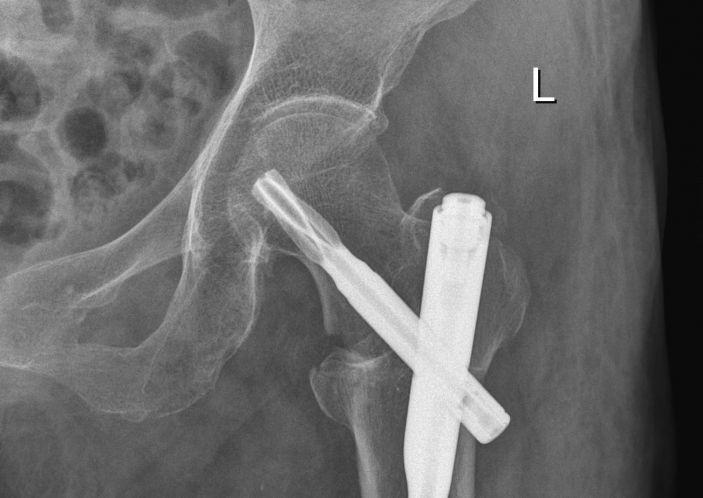

康美醫院外四科随即請内科、麻醉科等相關科室主任會診,經綜合評估,拟定詳細的治療方案。外四科吳主任決定盡早爲其開展微創手術治療,3月11日,在麻醉科和内科的配合下,吳主任帶領團隊成功爲黃婆婆施行左股骨粗隆間骨折閉合複位股骨近端髓内釘(PFNA)内固定手術,整個手術過程隻用了25分鍾左右,手術非常成功。術後醫護人員對其進行周密觀察、精心護理,患者恢複良好,已經康複出院。

據吳主任介紹,股骨近端髓内釘(PFNA)内固定手術屬于微創手術,具有手術切口小、創傷少、出血少、恢複快等優點。此次爲百歲高齡患者開展股骨微創手術體現我院外四科團隊的精湛技術,以及本院多科室配合綜合診治能力在本地區處于領先水平。